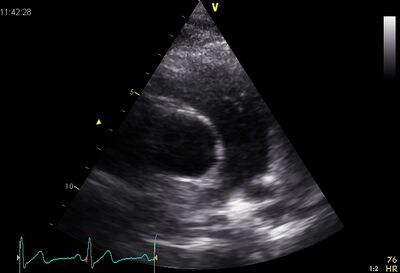

| Plax by tilted (Plax PV) | PSax Ao |

|---|---|

| Suprasternal apd (color doppler) | Dilated apd (Plax PV) |